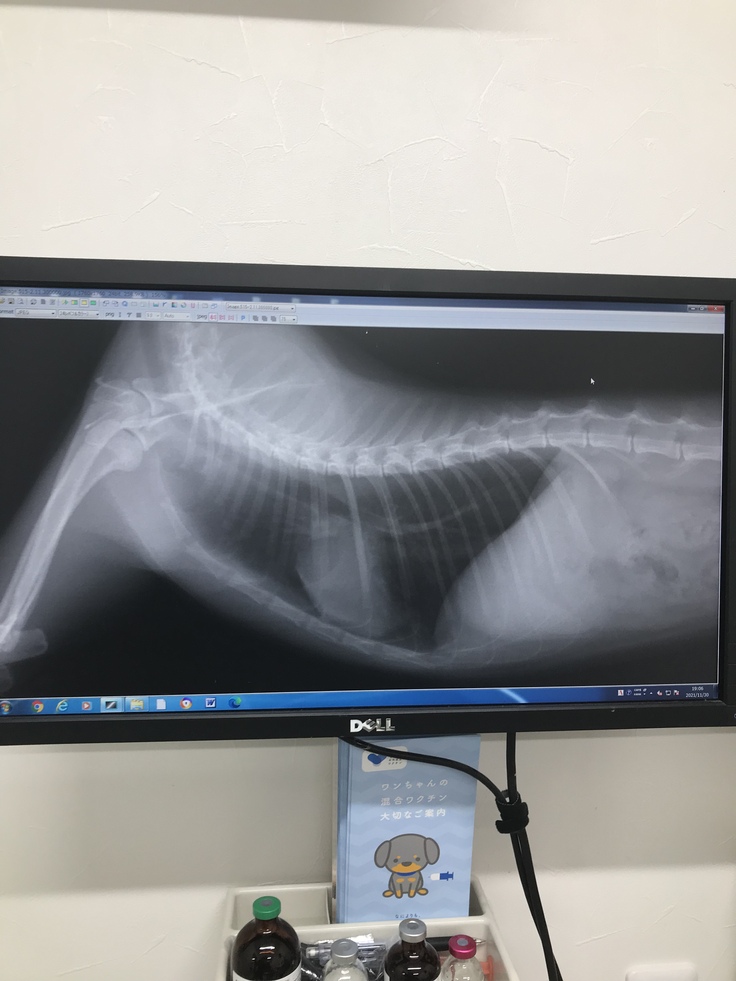

最新のレントゲンです。(2022/8/7撮影)

病院様に記載許可を頂いています。

よく出る副作用である吐き気もないようで、本当に穏やかに元気に生きてくれています。

先生からは、再燃の可能性は十分にあるので、心に準備はいつでもしておいてくださいと言われています。